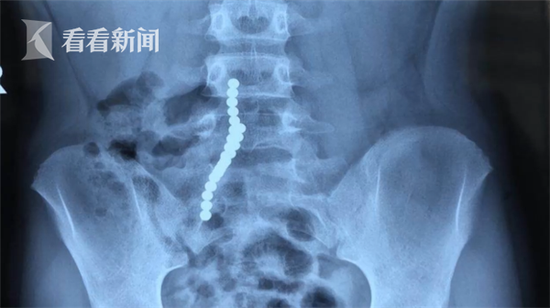

福州某医院泌尿外科主任说,这一串串起来,别看这样子,其实它里面是分散开的,因为没有拍侧位,等于二十二粒好像在一起,其实在里面是分开的。

泌尿内科主任称,这个手术用了五个多小时,从十二指肠到小肠、大肠,总共取了二十二粒磁力珠出来。

这些就是从患者体内取出的磁力珠,有些已经被胃液腐蚀发黑,医生介绍说,这些珠子可以摆成串就是因为它们具有很强的磁性,而导致患者肠壁破损的就是磁力的影响。